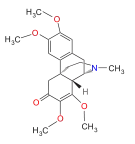

Others

- 1-Nitroaknadinine * 14-episinomenine

- 5,6-Dihydronorsalutaridine

- 6-Keto Nalbuphine

- Aknadinine

- Butorphanol

- Cephakicine

- Cephasamine

- Cyprodime

- Drotebanol

- Fenfangjine G

- Ketorfanol

- Nalbuphine

- Nalbuphone

- Tannagine

Structures

| Other Morphinans | ||||

|---|---|---|---|---|

1-Nitroaknadinine 1-Nitroaknadinine |

14-episinomenine 14-episinomenine |

5,6-Dihydronorsalutaridine 5,6-Dihydronorsalutaridine |

6-Keto Nalbuphine 6-Keto Nalbuphine |

Aknadinine Aknadinine |

Butorphanol Butorphanol |

Cephakicine Cephakicine |

Cephasamine Cephasamine |

Cyprodime Cyprodime |

Drotebanol Drotebanol |

Fenfangjine G Fenfangjine G |

Nalbuphine Nalbuphine |

Sinococuline Sinococuline |

Sinomenine Sinomenine |

Tannagine Tannagine |